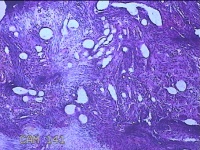

宫腔内容物

性别

女

年龄

45岁

临床诊断

子宫内膜息肉

一般病史

宫腔异常回声3月。

标本名称

大体所见

灰白暗红色不规则碎组织3x2x0.8cm一堆。

图1